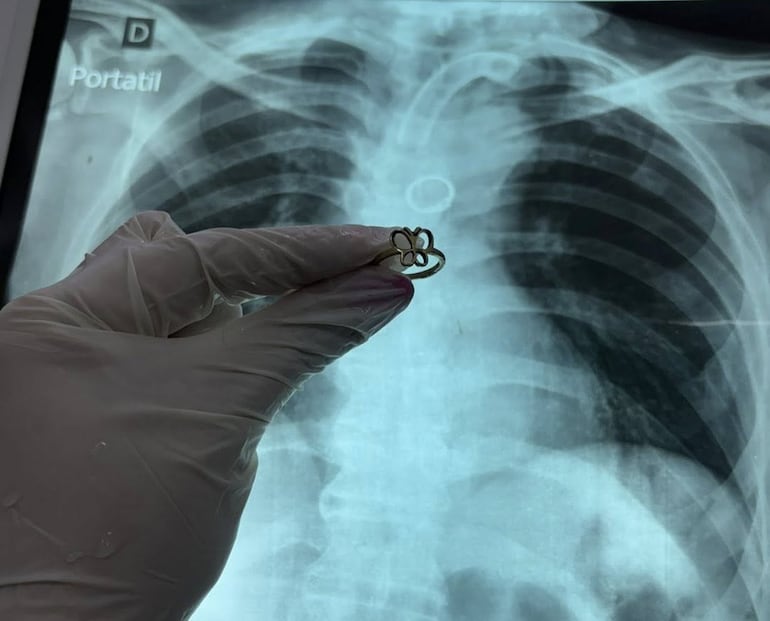

Ante la situación, los especialistas optaron por retirar la cánula traqueal e ingresar con un broncoscopio rígido por la vía oral. Finalmente, lograron ubicar y extraer el objeto.

“El anillo estaba brillando donde nunca debería estar”, describió el médico.

Más allá del éxito del procedimiento, el caso deja un interrogante central: ¿cómo llegó un anillo al pulmón de un paciente traqueostomizado?

Según el relato médico, no se detectaron obstrucciones ni alteraciones en la vía aérea superior que expliquen el ingreso del objeto. Tampoco se precisó en qué momento pudo haber ocurrido.